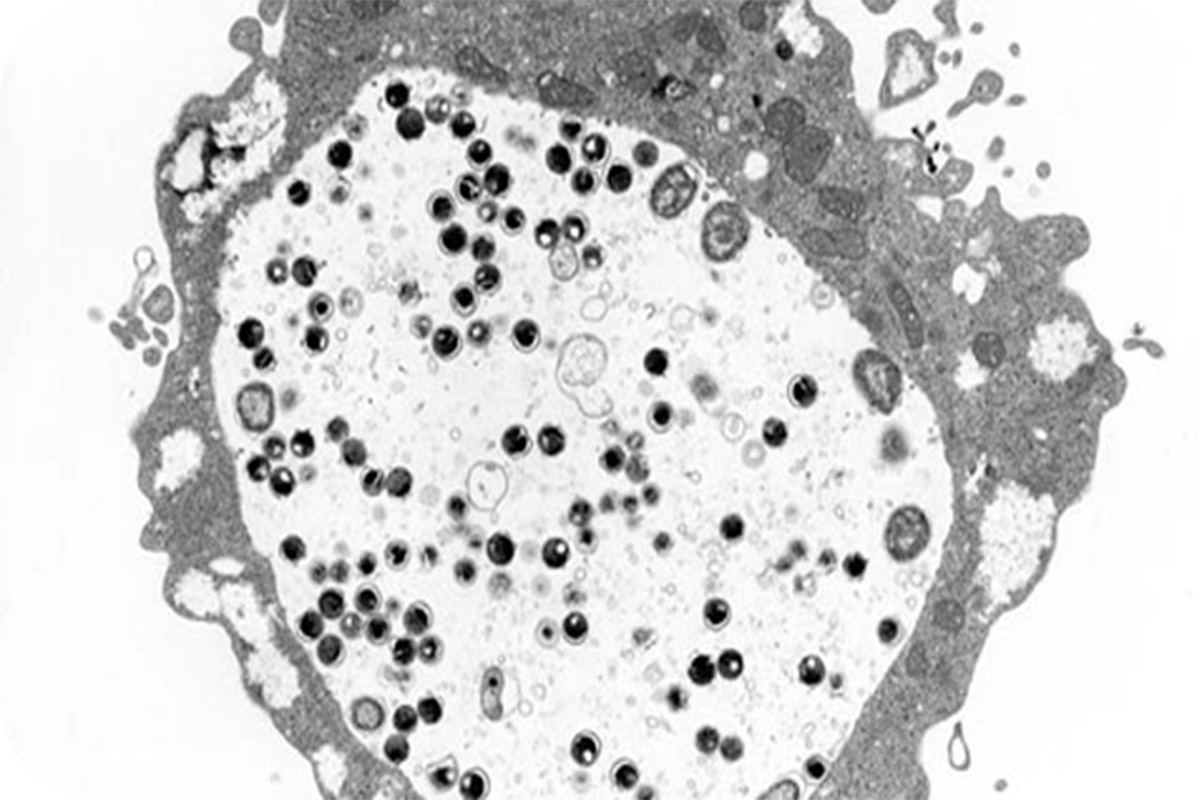

参照:国立感染症研究所